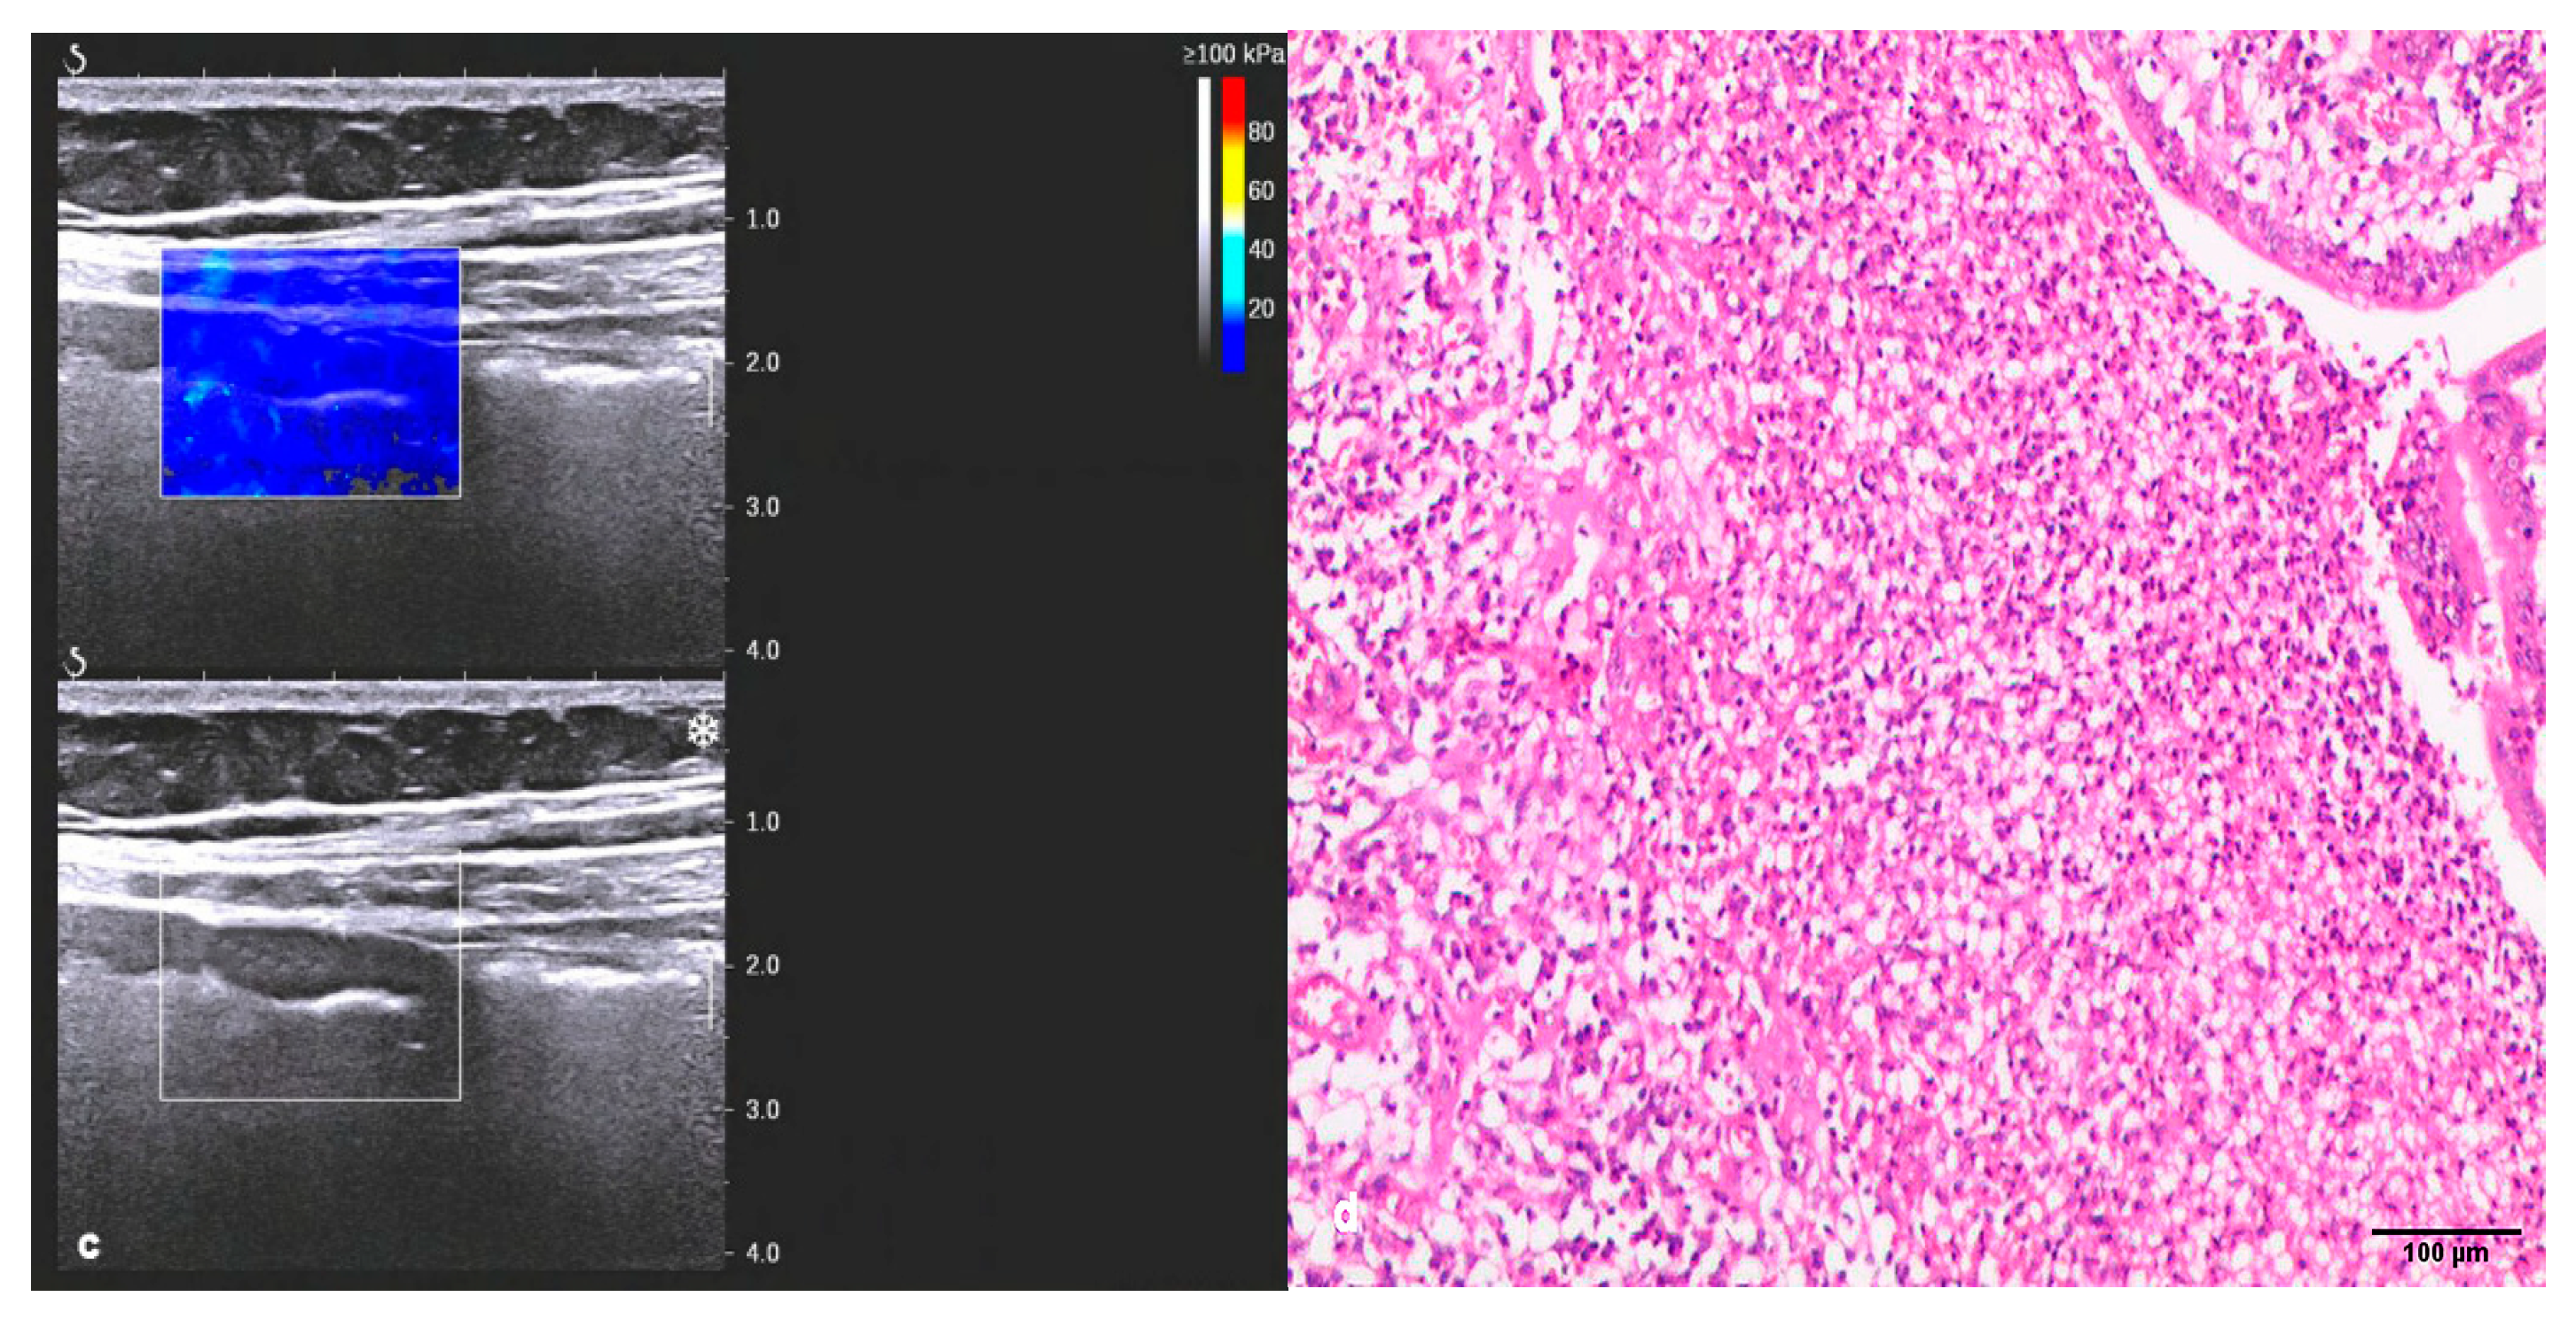

3.1. Conventional Ultrasound and Two-Dimensional Shear-Wave Elastography (2D-SWE)

| Inflammation | Fibrosis | p-Value | |

|---|---|---|---|

| Bowel wall thickness (mm) | 9.07 ± 4.14 | 10.53 ± 3.66 | NS |

| Limberg grading, n (%) | NS | ||

| I | 0 (0.00) | 1 (5.56) | |

| Ⅱ | 2 (10.53) | 8 (44.44) | |

| Ⅲ | 12 (63.16) | 7 (38.89) | |

| Ⅳ | 5 (26.32) | 2 (11.11) | |

| 2D-SWE, Emean, Kpa | 17.59 ± 7.21 | 35.24 ± 13.31 | 0.000 * |